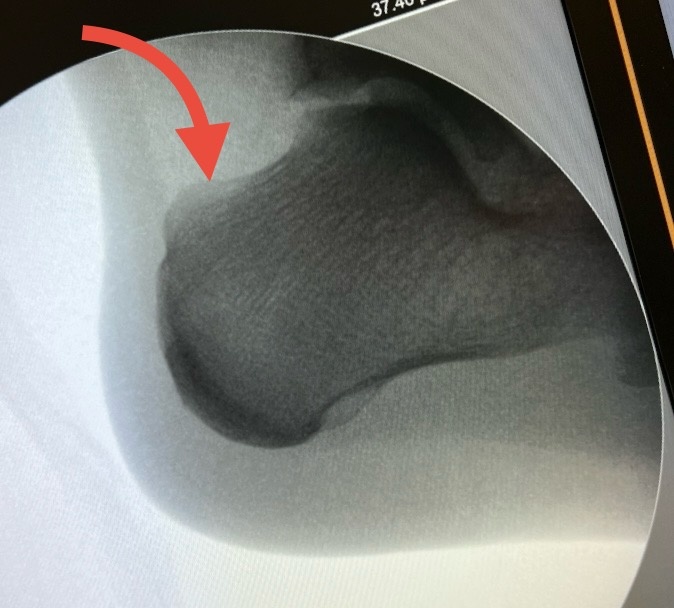

Речь пойдёт об экзостозе Хаглунда. Это такой выступ на пяточной кости, который изнутри давит на мягкие ткани, которые, упираясь в задник обуви, наминаются и болят.

На рентгенограмме шишка выглядит вот так:

Вроде небольшая, но кзади от неё имеется слизистая сумка, потом ахиллово сухожилие, потом еще одна слизистая сумка. Когда всё наминается, вырабатывается лишняя отёчная жидкость, появляется отёк пятки, что еще больше усугубляет проблему. Если еще и кожу растереть до пузырей, а там и инфекция присоединится - совсем плохо.